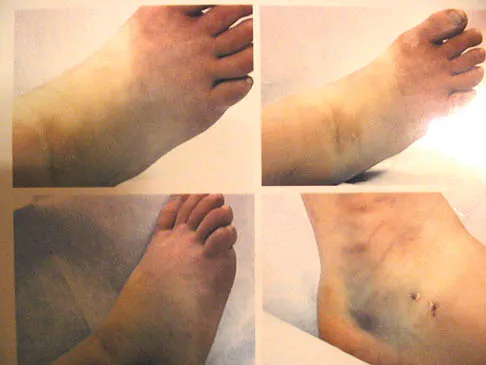

An 11-year-old girl sustained an injury to her right foot when a 500-lb headstone fell on it. The headstone was removed after 3 minutes. Radiographs show multiple midfoot fractures. Examination reveals severe pain that is worse with passive toe motion. Clinical photographs are shown in Figure 28. Management should consist of

Explanation